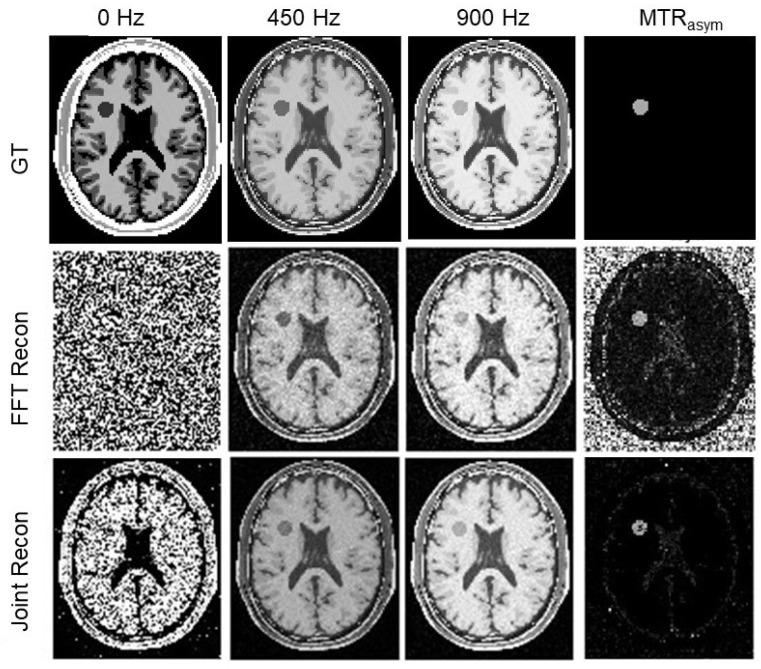

Chemical exchange saturation transfer (CEST) magnetic resonance imaging (MRI) is a novel MRI technology to image certain compounds at extremely low concentrations. Long acquisition time to measure signals at a set of offset frequencies of the Z-spectra and to repeat measurements to reduce noise pose significant challenges to its applications. This study explores correlations of CEST MR images along the spatial and Z-spectral dimensions to improve MR image quality and robustness of magnetization transfer ratio (MTR) asymmetry estimation via a joint -ω reconstruction model. The model was formulated as an optimization problem with respect to MR images at all frequencies ω, while incorporating regularizations along the spatial and spectral dimensions. The solution was subject to a self-consistency condition that the Z-spectrum of each pixel follows a multi-peak data fitting model corresponding to different CEST pools. The optimization problem was solved using the alternating direction method of multipliers. The proposed joint reconstruction method was evaluated on a simulated CEST MRI phantom and semi-experimentally on choline and iopamidol phantoms with added Gaussian noise of various levels. Results demonstrated that the joint reconstruction method was more tolerable to noise and reduction in number of offset frequencies by improving signal-to-noise ratio (SNR) of the reconstructed images and reducing uncertainty in MTR asymmetry estimation. In the choline and iopamidol phantom cases with 10.5% noise in the measurement data, our method achieved an averaged SNR of 31.0 dB and 32.2 dB compared to the SNR of 24.7 dB and 24.4 dB in the conventional reconstruction approach. It reduced uncertainty of the MTR asymmetry estimation over all regions of interest by 54.4% and 43.7%, from 1.71 and 2.38 to 0.78 and 1.71, respectively.